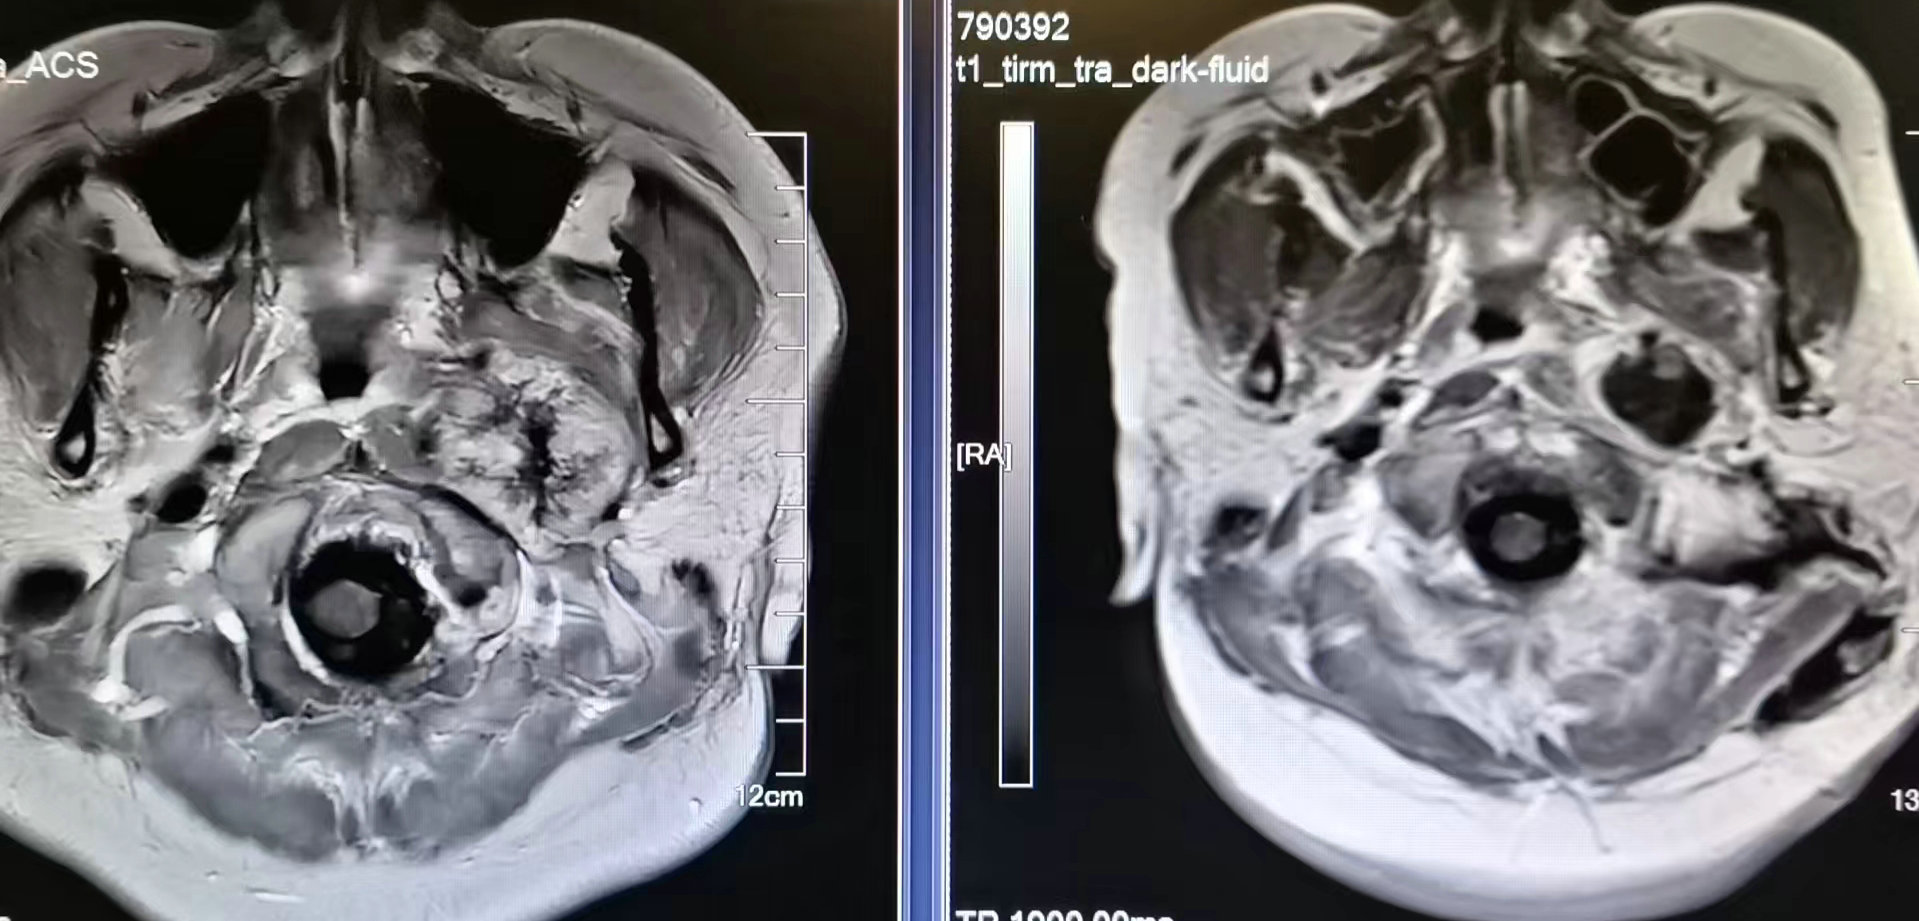

术前磁共振